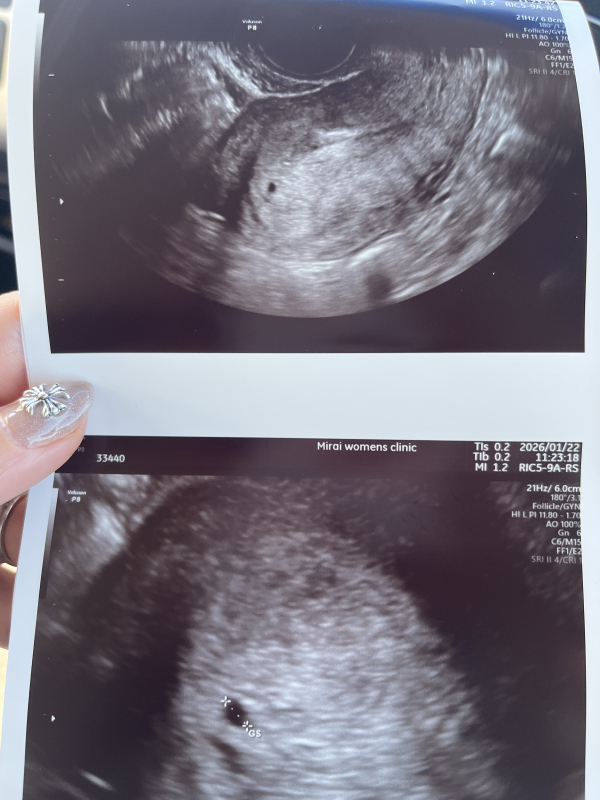

今日妊婦健診に行った所胎嚢がみえず。

先生がうまく育ってないか子宮外妊娠の可能性があるとhcgも測って出血もしてるので止血剤がでて今日の診察は終わりました。

最終生理が12/14なので5週目に入るタイミングで胎嚢もみえず頭真っ白です。はやりこれは流産の可能性が高いのでしょうか。

今日の診察で胎嚢が確認出来なかったということで、流産の可能性が高いのかご不安になられているのですね。

排卵のタイミングがいつ頃になるのかわからないこともありますので、はっきりとしたお返事が難しくなります。